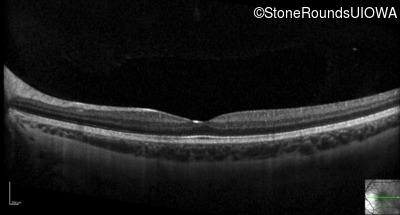

Optical Coherence Tomography - Right - 20/50 -1

Exemplar / OCT Stack